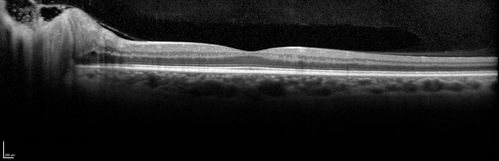

Syphillitic Optic Neuropathy and Maculopathy

46 year old woman with 2 weeks of vision loss OD.  VA 20/200 OD; 20/20 OS.  there are posterior vitreous cells on OCT in both eyes.  ICG, FAF, and FA show an abnormal macula OD.  VA improved to 20/30 within a month with treatment with PCN.